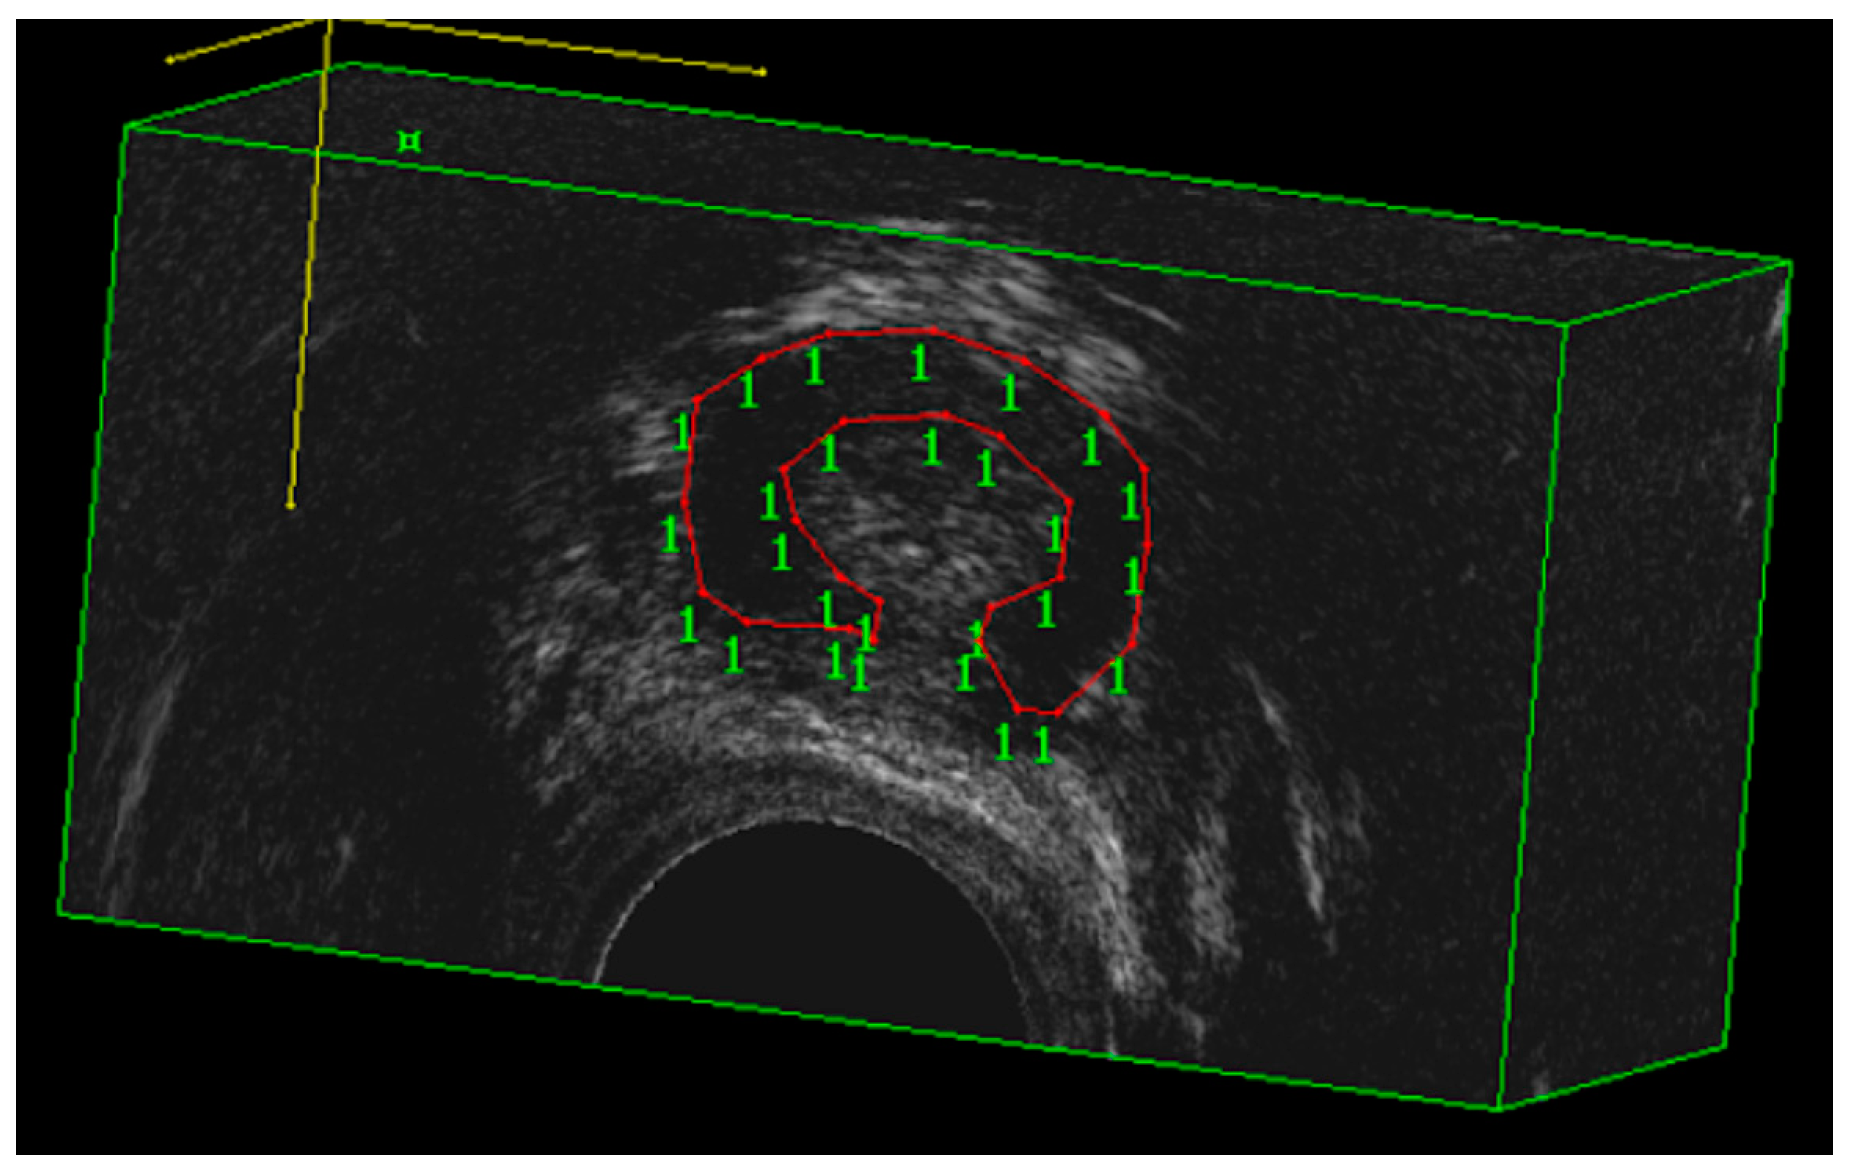

- Spelzini, F.; Cesana, M.C.; Verri, D.; Polizzi, S.; Frigerio, M.; Milani, R. Three-dimensional ultrasound assessment and middle term efficacy of a single-incision sling. Int. Urogynecol. J. 2013, 24, 1391–1397. [Google Scholar] [CrossRef]

- Hegde, A.; Rostaminia, G.; Quiroz, L.H.; Shobeiri, A.; Aguilar, V.C.; Davila, G.W. Are there age-related changes in the measurements of the urethral sphincter complex in nulliparous women? A three-dimensional ultrasound assessment. Int. Urogynecol. J. 2021, 32, 653–659. [Google Scholar] [CrossRef]

- Toozs-Hobson, P.; Khullar, V.; Cardozo, L. Three-dimensional ultrasound: A novel technique for investigating the urethral sphincter in the third trimester of pregnancy. Ultrasound Obstet. Gynecol. 2001, 17, 421–424. [Google Scholar] [CrossRef]

- Athanasiou, S.; Khullar, V.; Boos, K.; Salvatore, S.; Cardozo, L. Imaging the urethral sphincter with three-dimensional ultrasound. Obstet. Gynecol. 1999, 94, 295–301. [Google Scholar] [CrossRef]

- Digesu, G.A.; Robinson, D.; Cardozo, L.; Khullar, V. Three-dimensional ultrasound of the urethral sphincter predicts continence surgery outcome. Neurourol. Urodyn. 2009, 28, 90–94. [Google Scholar] [CrossRef]

| T0 Urethral rhabdosphincter volume (cm3) | 2.5 ± 0.9 | 2.5 ± 0.6 | 0.848 |

| URS volume (cm3) | 2.5 ± 0.9 | 2.9 ± 1.1 | <0.001 | 2.5 ± 0.6 | 2.6 ± 0.6 | 0.248 |

| T1 Urethral rhabdosphincter volume (cm3) | 2.9 ± 1.1 | 2.6 ± 0.6 | <0.001 |